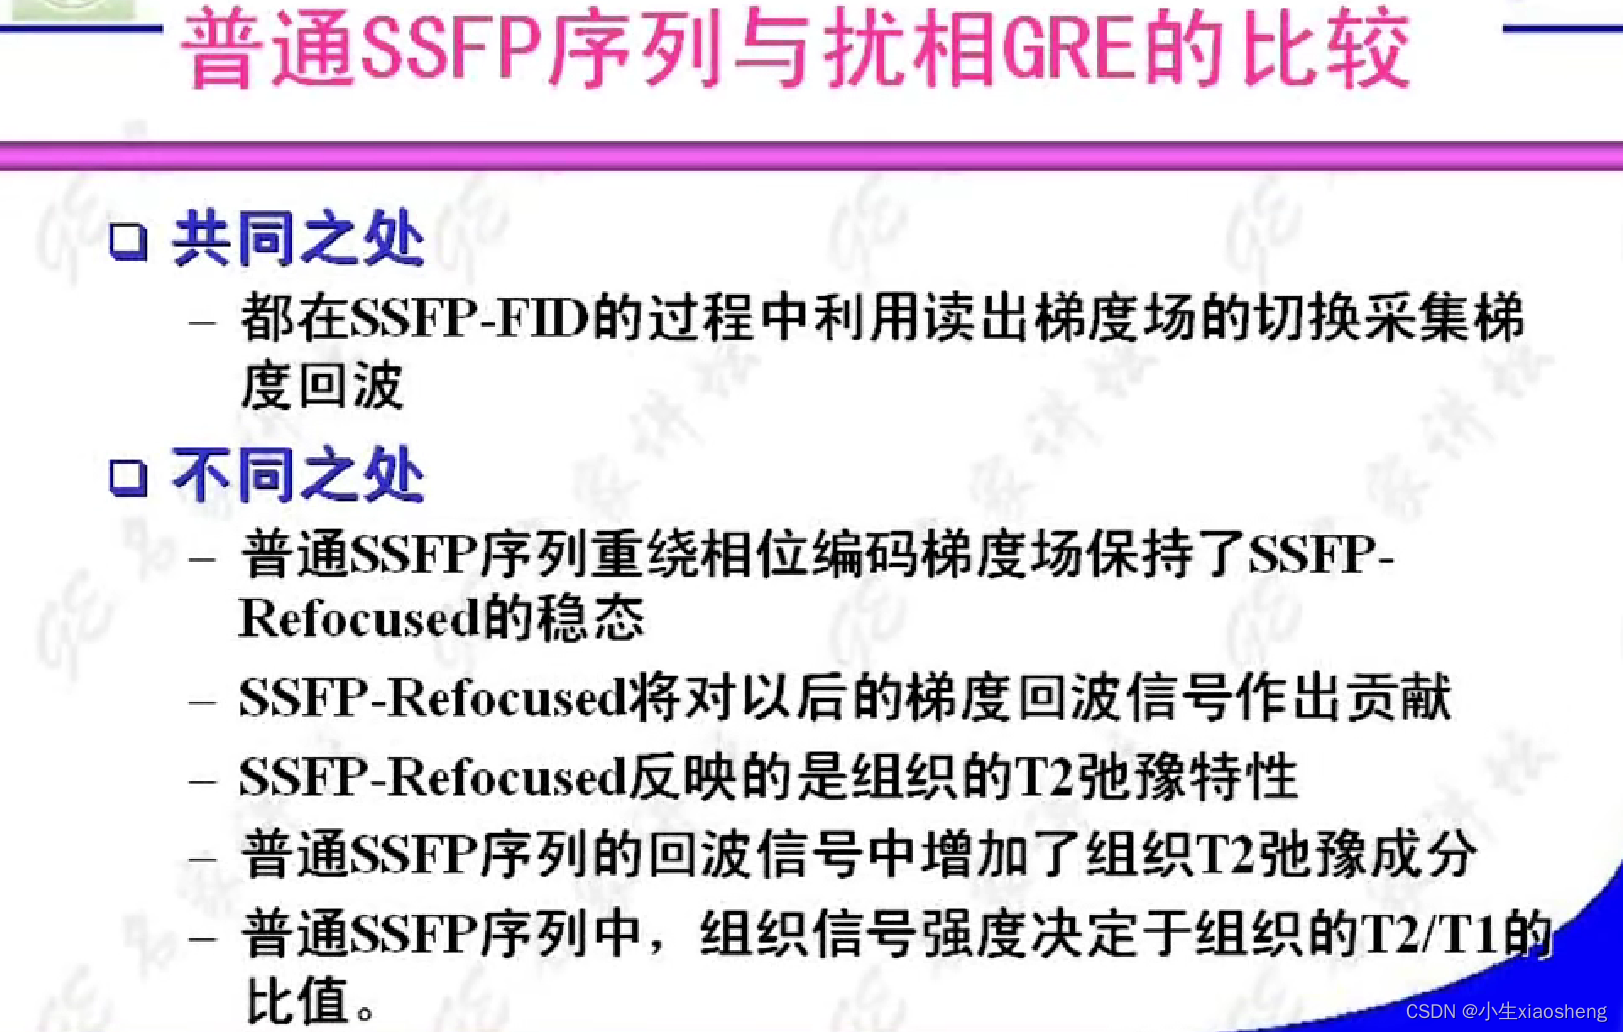

2.普通SSFP序列

梯度场抵消:SSFP序列的一个显著特点是,在Gx、Gy、Gz三个方向梯度场的正反切换完全抵消。这种抵消作用使得流动的信号得到补偿,从而在图像中减少或消除流动伪影。

在实际应用中,SSFP序列通常用于心脏成像、血管成像和腹部成像等领域。由于其较快的扫描速度和较高的信噪比,SSFP序列可以大大提高成像效率和质量。然而,SSFP序列也存在一些局限性,例如对磁场不均匀性较为敏感,可能产生伪影等。因此,在实际应用中需要根据具体情况选择合适的成像参数和扫描方法。

此外,SSFP序列还与其他技术相结合,形成了多种改进型的SSFP序列,如平衡SSFP(Balanced SSFP)序列等。

1.扰相梯度回波GRE

在SSFP成像中,如果每个SSFP-REF能够保持稳态,那么就可以利用这些回波信号来重建高质量的MRI图像。然而,由于各种因素的影响(如磁场不均匀性、组织特性等),SSFP-REF可能会发生变化,这可能会导致图像伪影(如带状伪影)的出现。而扰相主要用于提高成像速度和消除图像伪影。扰相技术的主要目的是在前一次射频脉冲(α脉冲)的MR信号采集后,对组织中的质子群的相位进行干扰,使其失相位加快,从而消除残留的横向磁化矢量。